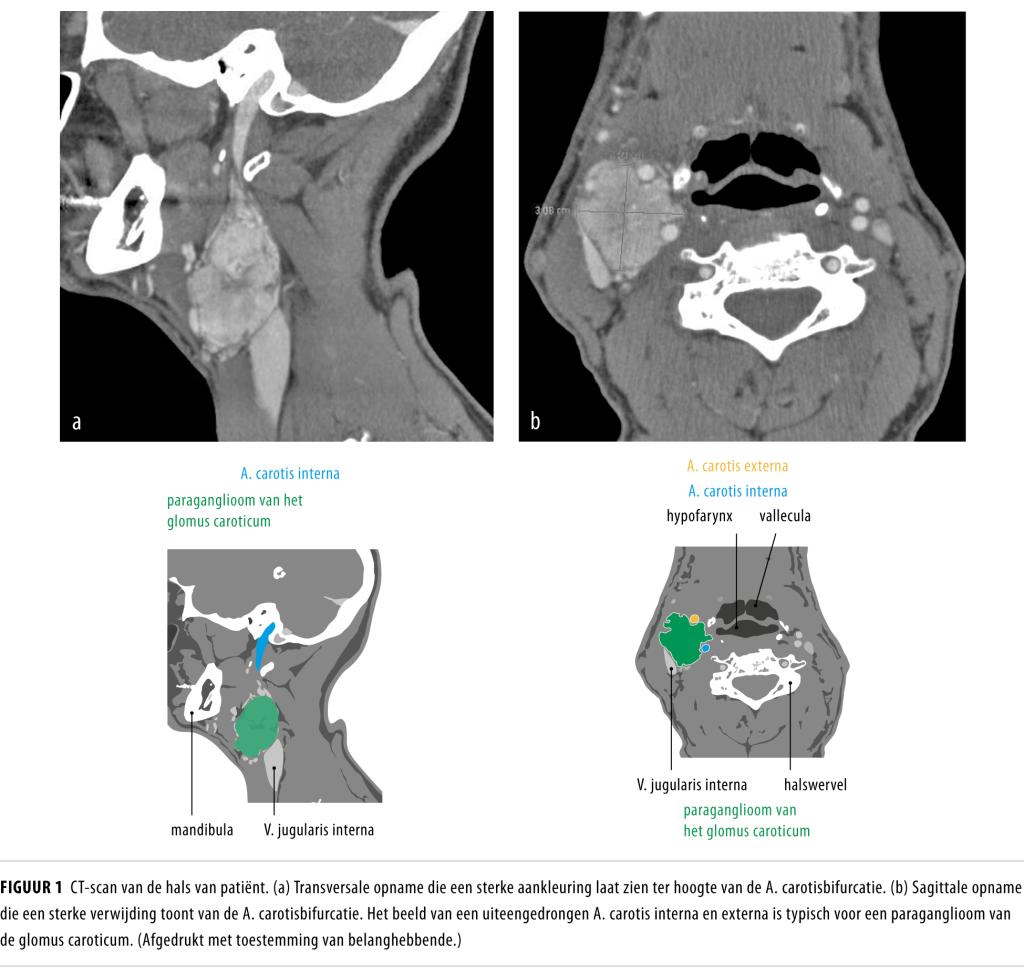

Een paraganglioom van het glomus caroticum is een zeldzame tumor in de hals die ontstaat ter hoogte van de carotisbifurcatie.

Een 52-jarige man werd verwezen met een zwelling rechts in zijn hals die al 10 jaar bestond. Uit beeldvormend onderzoek bleek er sprake te zijn van een paraganglioom van het glomus caroticum. Er was geen hormonale activiteit van de tumor en er waren geen andere paraganglioomlokalisaties. We verwijderden de tumor chirurgisch. Histologisch onderzoek bevestigde de diagnose paraganglioom. Genetisch onderzoek toonde dat patiënt drager was van een mutatie in het succinaatdehydrogenasesubunit D-gen.